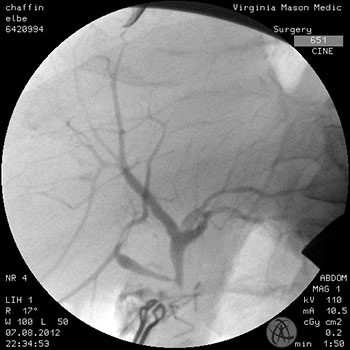

Intraoperatively, we found the gallbladder remained in situ with multiple gallstones and obliteration of the cystohepatic window (Mirizzi syndrome) to the side of the common bile duct due to associated inflammation. A cholangiogram was obtained confirming a transected common bile duct just above the cystic duct (Figure 2).

Figure 2. Intraoperative cholangiogram demonstrating an E1 biliary injury with aberrant anatomy. The right posterior section duct inserts low just above the transected common bile duct.